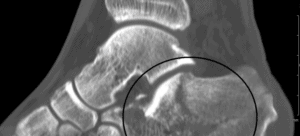

Prelom kosti dijagnoza

postavlja se kliničkim pregledom i snimanjima – najčešće rendgen, MR ili CT pregled.